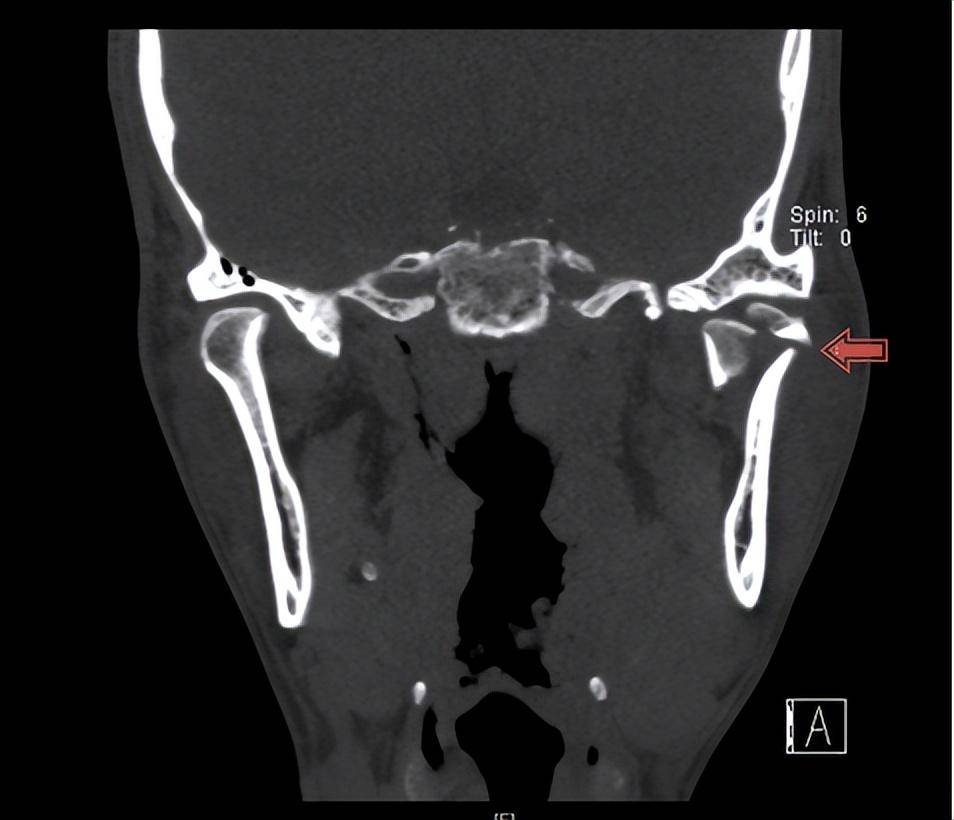

左侧下颌角周围软组织积气;右侧颞下颌关节向前移位.

图片尺寸936x804